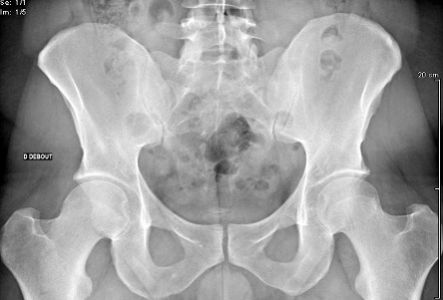

Radiographie

En savoir plus

Densitométrie Osseuse